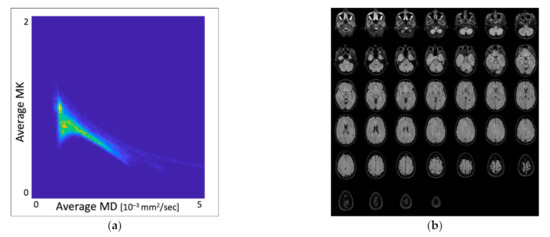

3.1. Distribution of MK and MD Values in Whole-Brain DKI Maps

3.2. Overlap Analysis